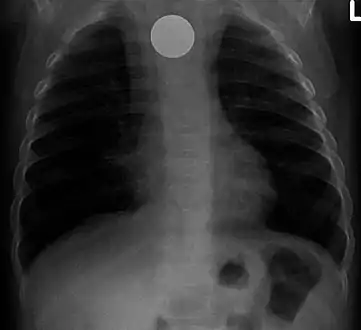

Multiple button batteries in the stomach